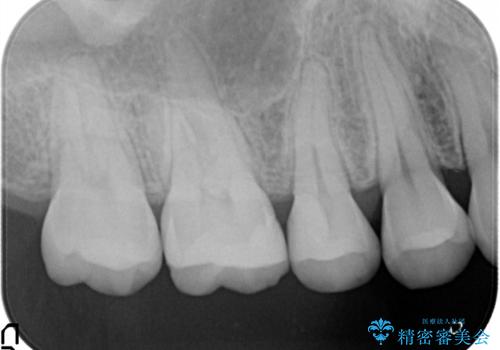

- 虫歯の治療を主訴に来院されました。メタルフリーによる治療を希望されましたので、セラミックインレーにて修復治療を行っております。

- 14万円(セラミックインレー×2)費用は治療当時の料金となります

当院でのセラミックインレーはすべてe-maxと呼ばれる高強度セラミックにて製作されます。

また、製作方法もプレスと呼ばれる方法を用いることで精度を高めています。